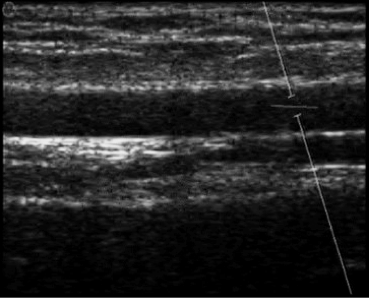

For FMD Studio we recommend an image depth of 2-3 cm. It is suggested also to choose a projection so that the vein is not visible (this normally appears immediately above the brachial artery). The algorithm for automatic tracking of the edges of the vessel could recognize the edge of the vein instead of the artery.

images/download/attachments/381258618/en_Ultrasound_Brachial-version-1-modificationdate-1759328517236-api-v2.png

Example of brachial artery image